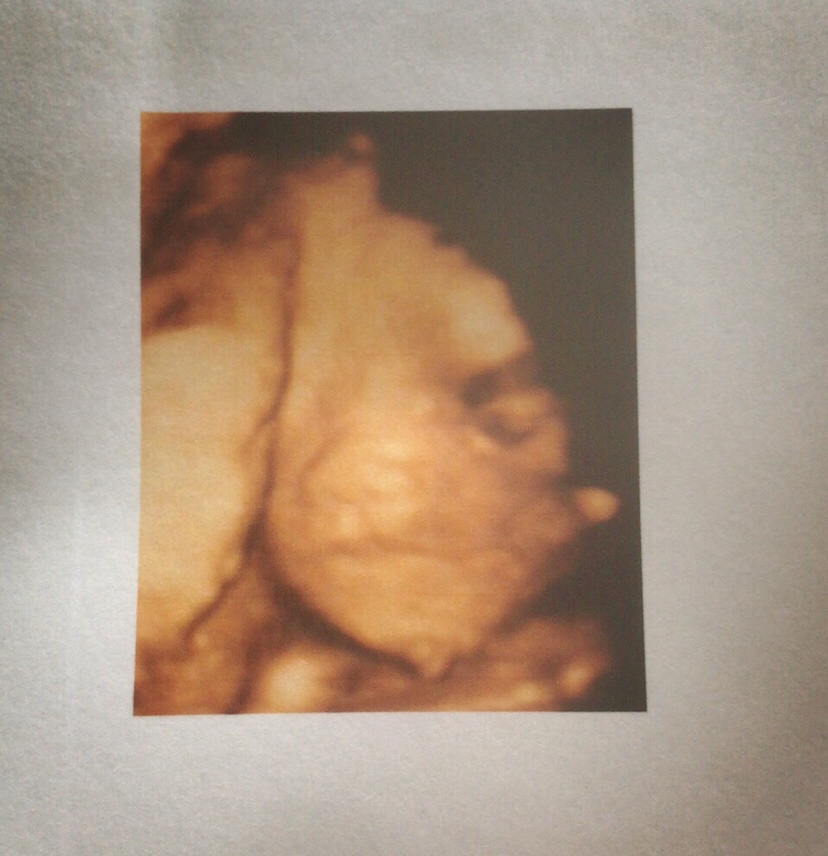

孕29周+6天

很可爱